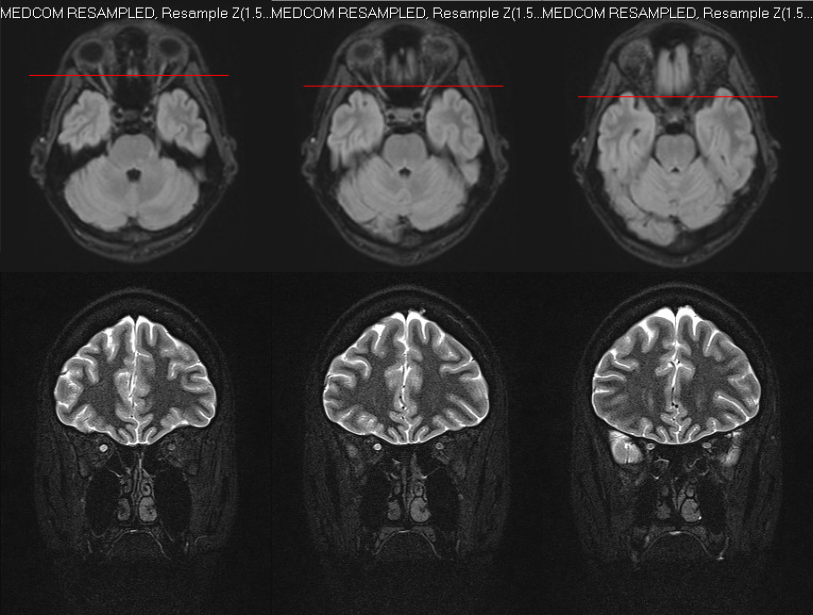

자기 공명 영상 (MRI)MRI 촬영 시, 시신경염의 영향을 받은 쪽 시신경에서 신호가 증가하는 소견이 나타난다.[1] 특히 급성기에는 조영제를 사용한 MRI 검사를 통해 시신경 및 신경초의 염증이나 부종을 확인할 수 있다.[1] 시간이 지나 발병 3개월 이상 경과하면 시신경 내부의 신호가 증가하여 밝게 보이기도 한다.[1] 또한, 두부 MRI는 탈수초성 질환과 같은 다른 신경계 질환의 동반 여부를 평가하는 데에도 유용하다.

광학 단층 촬영법 (OCT)OCT는 시신경 손상을 매우 민감하게 파악할 수 있는 정밀 영상 검사 방법이다.[1] OCT 검사를 통해 급성기에는 시신경 유두의 부종을 확인할 수 있으며, 발병 후 3개월 이상 지나면 눈과 뇌를 연결하는 신경 세포와 신경의 두께, 특히 망막 신경 섬유층(RNFL)의 두께가 감소하는 것을 관찰할 수 있다. 이때 양쪽 눈의 RNFL 두께 차이가 4-5% 이상 나타나기도 한다.[1] RNFL 두께의 양안 비대칭은 시신경염을 나타내는 강력한 지표로 제안되었다.[9][10][11] 또한, OCT 검사는 다발성 경화증과 시신경척수염을 감별하는 데 도움을 줄 수 있는데, 시신경척수염에서 RNFL의 얇아짐이 더 뚜렷하게 나타나는 경향이 있다.